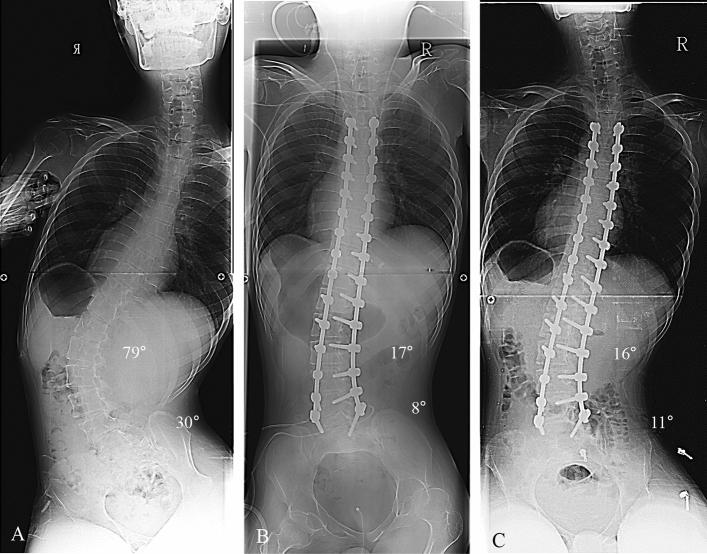

Pelvic fixation is performed to obtain proper coronal and sagittal alignment when the pelvic obliquity is more than 15º in patients with neuromuscular scoliosis (NMS). Since many NMS patients were wheelchair or bed-ridden status, there has been controversy on the effect of pelvic fixation. Therefore, the purpose of this study is to analyze the effects of pelvic fixation on correction of spinal deformity and quality of life (QoL) in NMS patients. A total of 77 NMS patients who underwent deformity correction were divided into three groups and retrospectively analyzed preoperatively, postoperatively, and at 2-year follow-up: pelvic fixation group (Group A, n = 16), fixed to S1 (Group B, n = 33), and fixed to L5 (Group C, n = 28). The correction rate of scoliosis was 60.0%, 58.0%, and 56.7% in groups A, B, and C, respectively, with no statistical difference (P > 0.05). The correction rate of pelvic obliquity was 61.3%, 42.8%, and 57.5% in respective groups A, B, and C, with no significance (P > 0.05). The correction loss of scoliosis and pelvic obliquity showed no statistical significance between three groups for 2-year follow-up (all Ps > 0.05). There were no significant differences regarding clinical outcomes and postoperative complications among the three groups (all Ps > 0.05). Therefore, pelvic fixation using iliac screws is not substantially influencing radiological and clinical outcomes in the patients with NMS.

骨盆固定术用于矫正神经肌肉性脊柱侧凸(NMS)患者骨盆倾斜超过 15°时的冠状位和矢状位对线。由于许多 NMS 患者处于轮椅或卧床状态,骨盆固定的效果存在争议。因此,本研究旨在分析骨盆固定对 NMS 患者脊柱畸形矫正和生活质量(QoL)的影响。共纳入 77 例接受畸形矫正的 NMS 患者,分为三组,回顾性分析术前、术后和 2 年随访时的情况:骨盆固定组(A 组,n=16),固定至 S1(B 组,n=33)和固定至 L5(C 组,n=28)。A、B 和 C 组的脊柱侧凸矫正率分别为 60.0%、58.0%和 56.7%,差异无统计学意义(P>0.05)。A、B 和 C 组骨盆倾斜矫正率分别为 61.3%、42.8%和 57.5%,差异无统计学意义(P>0.05)。三组患者术后 2 年随访时,脊柱侧凸和骨盆倾斜的矫正丢失无统计学差异(均 P>0.05)。三组患者的临床结果和术后并发症无显著差异(均 P>0.05)。因此,在 NMS 患者中,使用髂骨螺钉进行骨盆固定不会显著影响影像学和临床结果。